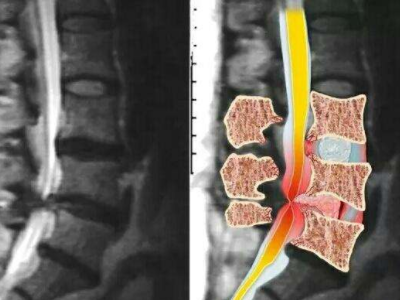

脊柱脊髓神经微创中心以微创技术为引领,以功能恢复为目标,主要治疗脊柱外伤、肿瘤、退行性病变、脊柱畸形等疾病。团队利用神经外科显微技术,结合神经内镜微创技术,对脊柱间盘变性疾病、颈腰椎管狭窄、颈腰椎间孔狭窄、颈腰椎间盘突出、颈腰椎体不稳、脊柱骨折、寰枢椎脱位、脊柱肿瘤、椎管内肿瘤、脊髓损伤、脊髓空洞、脊髓栓系等疾病进行高效、特色手术治疗,如颅颈交界区畸形寰枕减压内固定术、脊柱肿瘤全脊椎切除内固定术、微创椎管内肿瘤切除术、微创脊柱旁肿瘤切除术、寰枢椎脱位椎间融合内固定术、脊柱骨折微创经皮椎弓根钉内固定术、经椎间孔椎间融合内固定术(MIS—TLIF)等,最大程度降低脊柱脊髓手术创伤,具有创伤小、输血少、恢复快、口碑好,出院早等优势。

• 1椎管扩大成形术

• 2脊柱肿瘤全脊椎切除内固定术

• 3微创椎管内肿物切除术

• 寰枢椎脱位椎间融合内固定术 4

• 5脊柱骨折+腰椎滑脱-椎弓根钉内固定术

• 颈椎间盘切除、椎管减压术 6